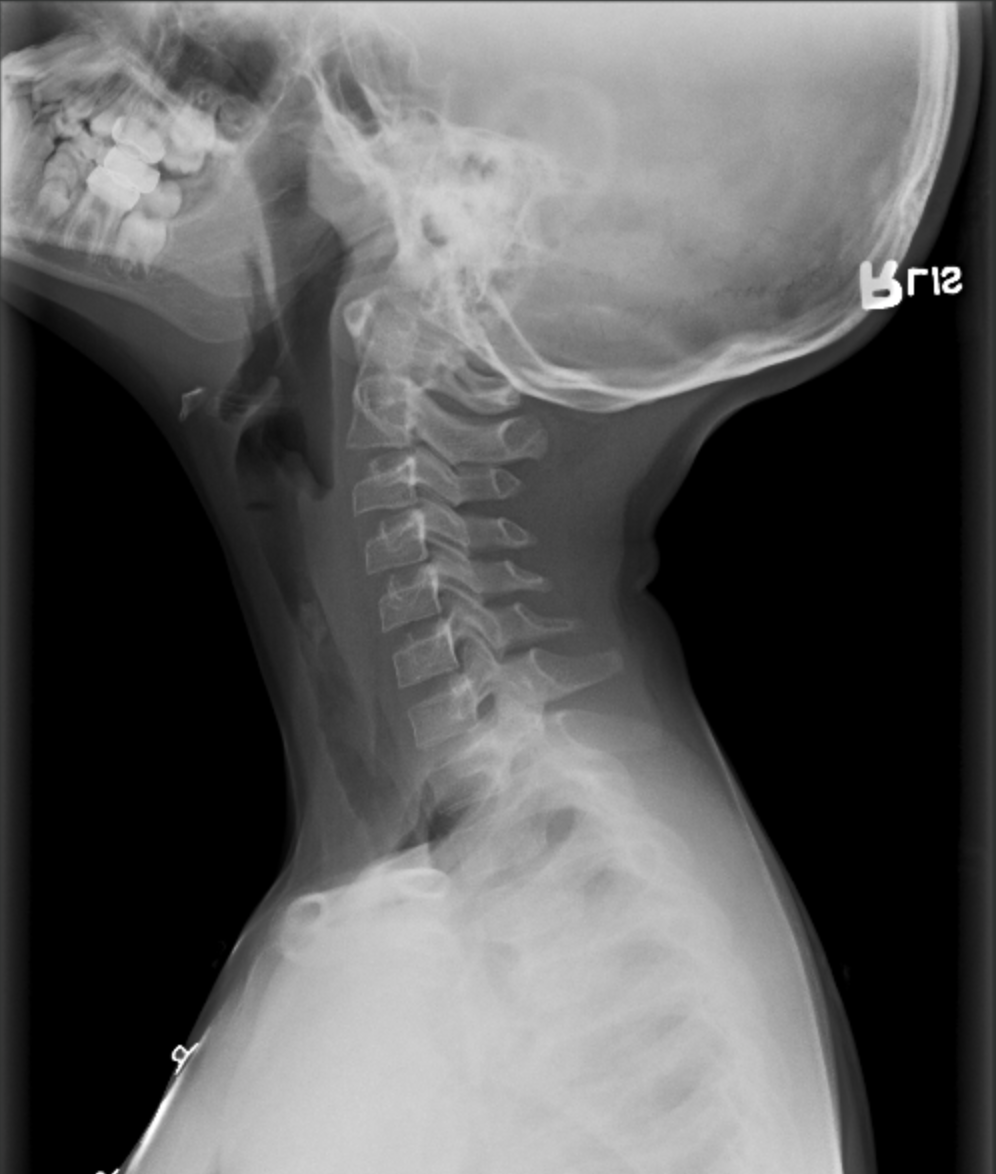

Laryngotracheobronchitis (Croup)

• Kids 6 months - 3 years old

• Steeple sign

• Subglottic tracheal edema

• Age 6 months -3 years

• Barky cough that may improve with exposure to cold air

• Parainfluenza virus

• Clinical diagnosis